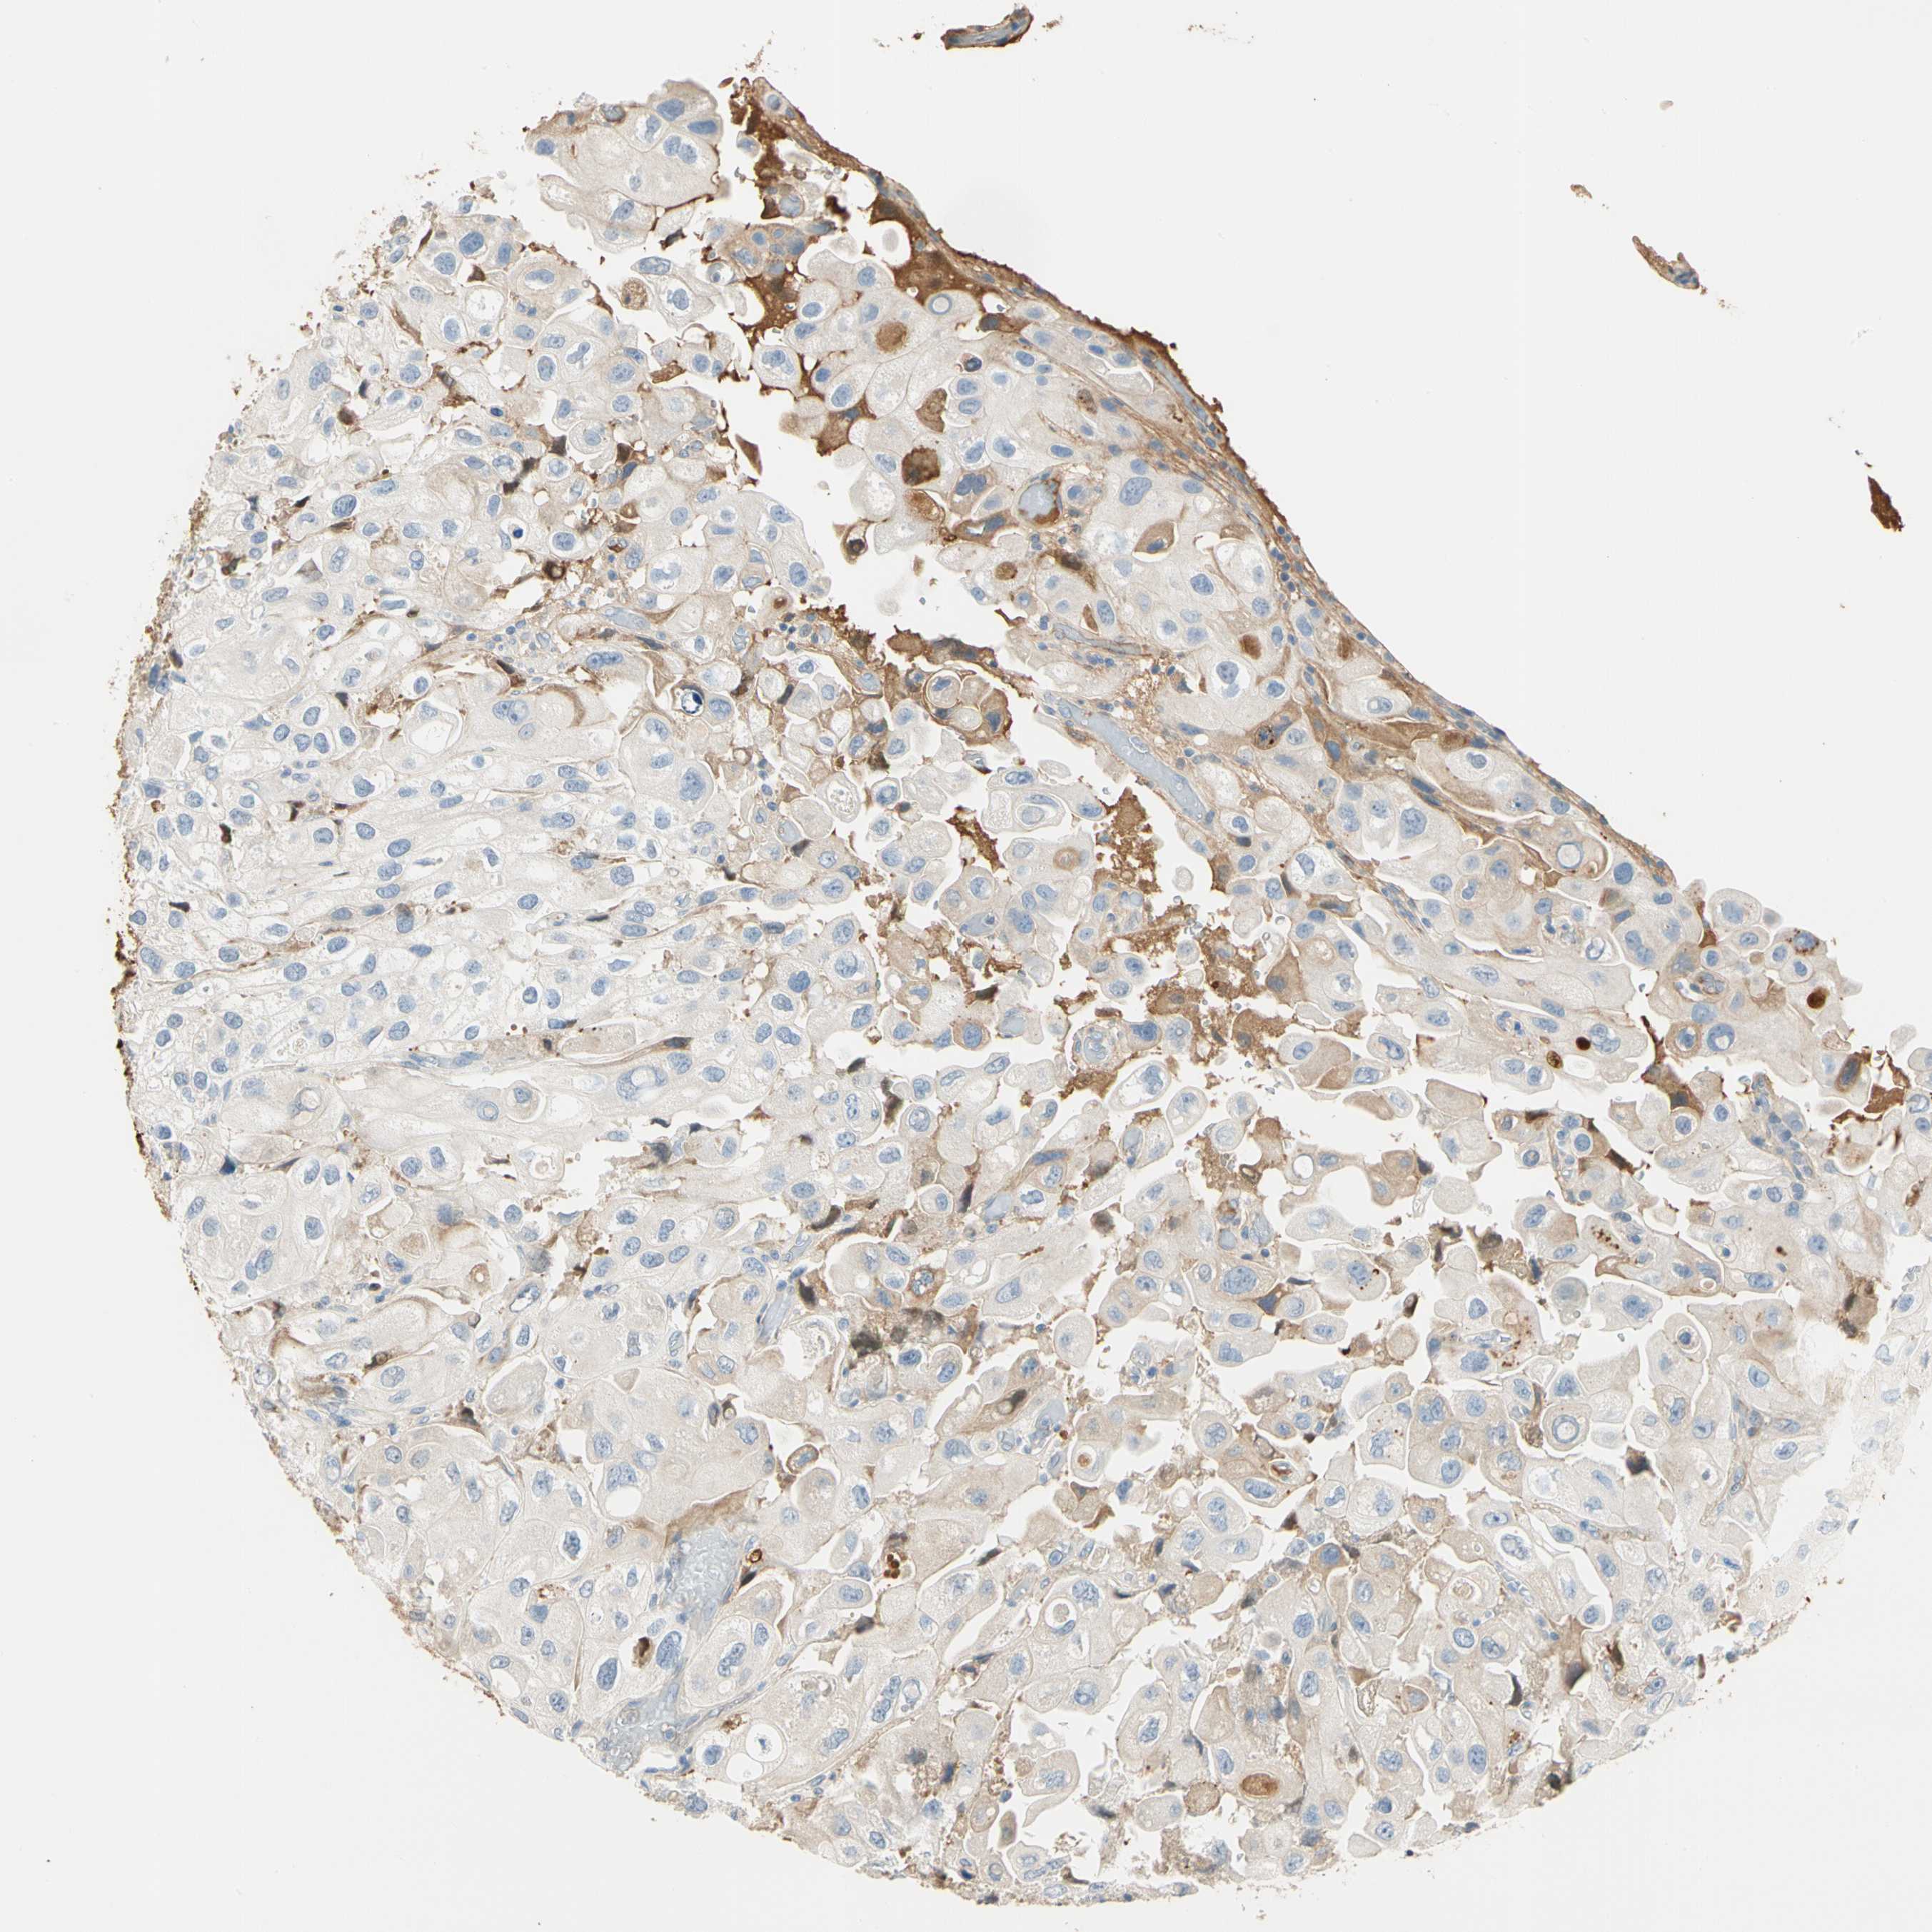

UROTHELIAL CANCER - Protein expressioni

A mouse-over function shows sample information and annotation data. Click on an image to view it in a full screen mode. Samples can be filtered based on level of antibody staining by selecting one or several of the following categories: high, medium, low and not detected. The assay and annotation is described here.

Note that samples used for immunohistochemistry by the Human Protein Atlas do not correspond to samples in the TCGA dataset.

Antibody stainingi

Antibody staining in the annotated cell types in the current human tissue is reported as not detected, low, medium, or high, based on conventional immunohistochemistry profiling in selected tissues. This score is based on the combination of the staining intensity and fraction of stained cells.

Each image is clickable and will lead to virtual microscopy that enables deeper exploration of all samples and also displays staining intensity scores, fraction scores and subcellular localization as well as patient and tissue information for each sample.

Antibody HPA008069

Antibody CAB078183

Staining

High

Medium

Low

Not detected

Intensity

Strong

Moderate

Weak

Negative

Quantity

>75%

75%-25%

<25%

None

Location

Nuclear

Cytoplasmic/membranous

Cytoplasmic/membranous,nuclear

Urothelial carcinoma, Low grade

Urothelial carcinoma, High grade

Urothelial carcinoma, NOS